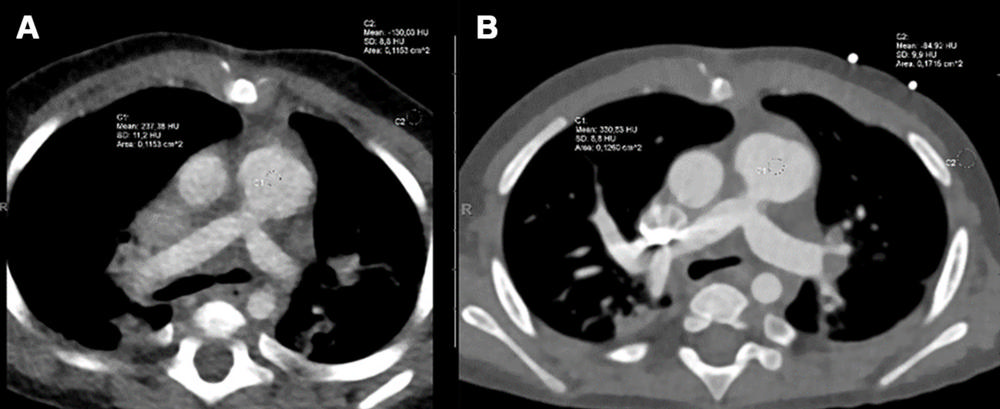

Figure 3. Axial contrast-enhanced dual-source CT (DSCT) and photon-counting CT (PCCT) images for comparison of image quality in the same infant who for clinical reasons underwent both (A) DSCT at 308 days old and (B) PCCT 14 days later at 322 days old. The male infant had a complete ventricular septum defect, Rastelli type A, postoperative situs after stenosis of the left and right lung veins and a so-called sutureless repair, banding of the pulmonary artery, and duct ligation. CT was performed again for clinical reasons (sonographic suspicion of pulmonary venous restenosis). On a five-point scale, the diagnostic image quality score of DSCT (A) was rated as moderate (score of 3), whereas that of PCCT (B) was rated as excellent (score of 5).